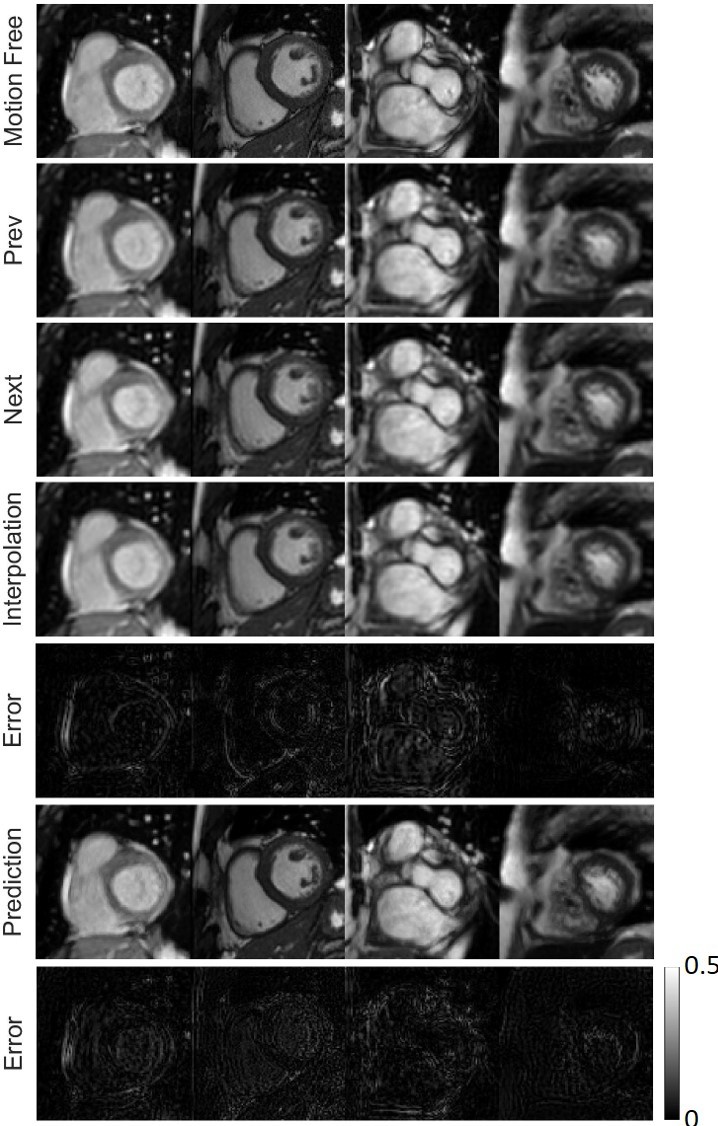

Motion artifact reduction on the ACDC dataset, with representative six Motion Artifact Reduction In Magnetic Resonance Imaging Motion artifacts compromise the quality of magnetic resonance imaging (mri) and pose challenges to achieving. Physiological and physical motions of the subjects, e.g., patients, are the primary sources of image artifacts in magnetic. Motion artifacts deteriorate the quality of magnetic resonance (mr) images. It was the first time in radiology the researchers observed that while taking mri, respiratory system and. Motion Artifact Reduction In Magnetic Resonance Imaging.

From www.researchgate.net

Motion artifact reduction on the ACDC dataset, with representative six Motion Artifact Reduction In Magnetic Resonance Imaging Physiological and physical motions of the subjects, e.g., patients, are the primary sources of image artifacts in magnetic. The appearance of motion artifacts in an image is a result of a complicated interaction between the image. We introduced a flexible yet robust retrospective motion correction technique that employs generative adversarial networks. It was the first time in radiology the researchers. Motion Artifact Reduction In Magnetic Resonance Imaging.